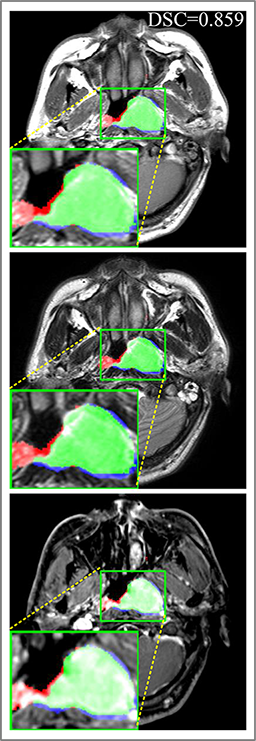

Comparison with ground truth. Some predicted results of MMFNet are shown in 2D images and 3D images in Figure 7 and Figure 8. As shown in these figures, although the shape and size of NPC are varied from each other, MMFNet can still accurately determine the regions of NPC and obtain the accurate contours of tumors. Through analyzing 2D images in figure 7, MMFNet has a capacity to fuse multi-modality MRI to reduce the confusion brought by intensity’ similarity between nearby tissues and NPC. The values of , and of MMFNet are shown in Table 1. MMFNet can reach the best results with , and .

Comparison with related works. Table 1 reports the values of , and for different methods. Predicted masks of different methods are illustrated in Figure 9 and Figure 10, which respectively present results in 2D and 3D images. Through comprehensively analyzing these results, the proposed MMFNet actually have the following properties:

(i) It directly fuses 3D MRI images rather than 2D slices. Thus, it can effectively use meaningful information from neighboring slices of MRI to realize NPC segmentation. As shown in Table 2, MMFNet can bring , and improvements in and compared to the best method based on 2D images (Multi-modality patch-based CNN). And Figure 10 shows that 3D-based methods have less isolated regions (false positives) than 2D-based ones.

(ii) It segments NPC by fusing multi-modality MRIs with the multi-encoder network. Thus, it can learn complementary and interdependent features from different modalities of MRI for final decisions. Additionally, comparing with input-level fusion networks and decision-level fusion networks, layer-level fusion networks (including MMFNet) can effectively capture informative features from different modalities of MRI and fuse low-level features and high-level features.

(iii) It uses a fusion block to fuse low-level features from different modalities of MRI and prepare these low-level features for the fusion with high-level features. Thus, it can more effectively fuse information from various sources. It also uses the self-transfer strategy to initialize the netwerk. Hereby, it can stimulate encoders to make full mining of meaningful features from modality-specific MRI. And it finally improve base multi-encoder-based network (Merging encoders’ fetures) by , and in and .